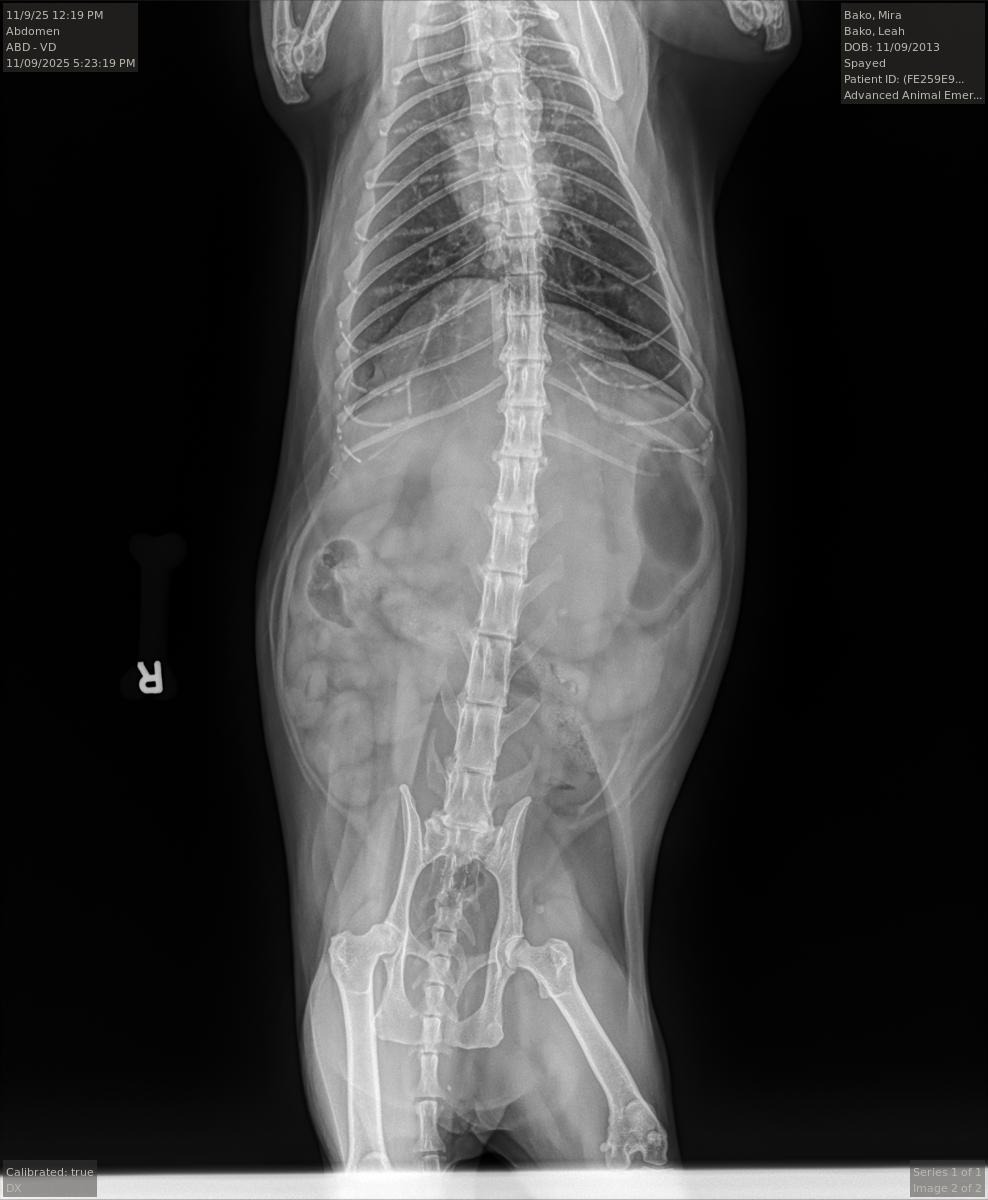

We rushed her to the veterinarian urgent care (the only closest one open on a Sunday), and the worst news imaginable hit us like a brick wall - the xray showed a large tumor on her liver that is pressing against her intestines. The veterinary team is optimistic that with surgery, Mira can recover and enjoy more precious time with her family.

Because it is a large tumor, they believe removing it can be curative as it does not seem like a fast-acting cancerous tumor, but there is no way I can afford this kind of treatment. It's a lot to process.